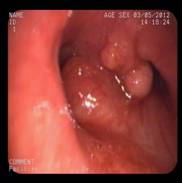

患者施某,男,49岁,1月前不明原因出现咳嗽、咯血,3月初入住我科,经支气管镜检查发现:气管近隆突处新生物,导致左右主支气管狭窄,尤其右侧明显,气管镜不能伸入。病理诊断:透明细胞肌上皮瘤。属罕见气管肿瘤,呈低度恶性。患者资料由家属送至上级医院会诊及我院全院讨论,无手术指征,因患者气道狭窄严重,随时可能因肿瘤增大出现呼吸困难及窒息,放化疗治疗因风险大暂不宜进行。我科于3月19日下午在DSA室行Y形气管支架植入术。术中,俞万钧主任负责介入操作,麻醉科严国章主任负责全麻、喉罩辅助通气及监护、DSA马霁波主任配合定位及支架释放,支架放置顺利完成,患者清醒后安返病房。

术中照片